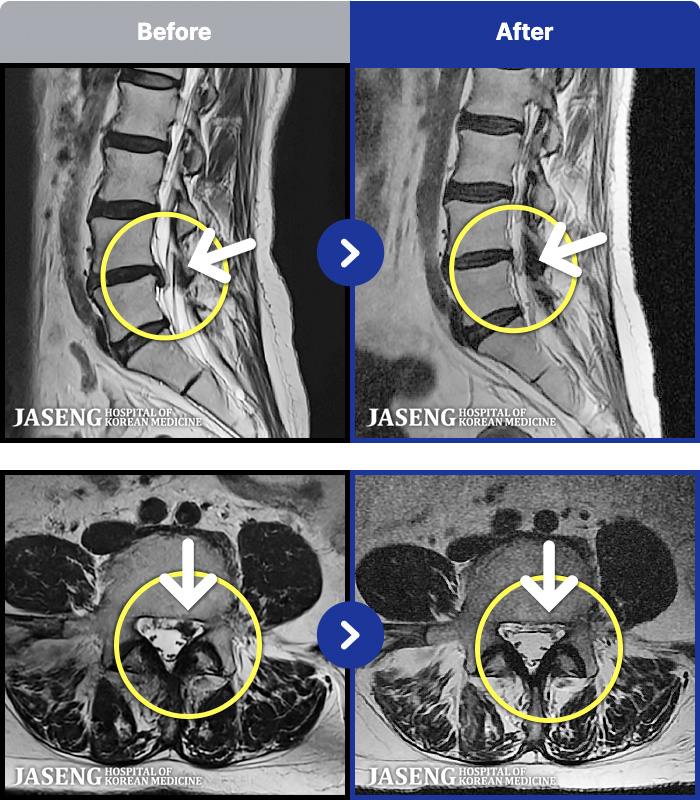

[ϻ] 24.07.25~25.08.01

ȯںп Ǹ ǿ ԿǾ, ο ġ ۿ Ƿ ġḦ Ͻñ ٶϴ.